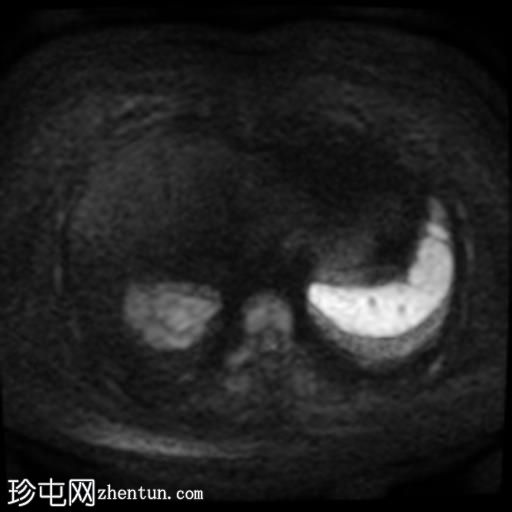

轴位

DWI序列

4.jpg

肝脏第7段可见一边界清晰的分叶状肿块。T1加权像呈低信号,T2/T2脂肪抑制序列呈高信号,动脉期呈不连续结节状周边强化,门静脉期呈向心性强化,延迟期完全强化。DWI序列呈高信号,ADC值呈混合信号。